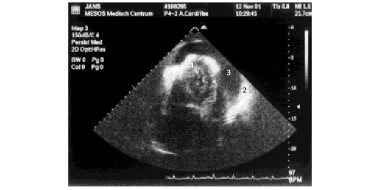

HELLP is een ernstige variant van pre-eclampsie, waarbij sprake is van hemolyse, transaminasenstijging en trombocytopenie (Hemolysis, Elevated Liver enzymes, Low Platelets). Bovenbuikpijn, misselijkheid en braken komen het vaakst voor bij het HELLP-syndroom en hebben de beste voorspellende…